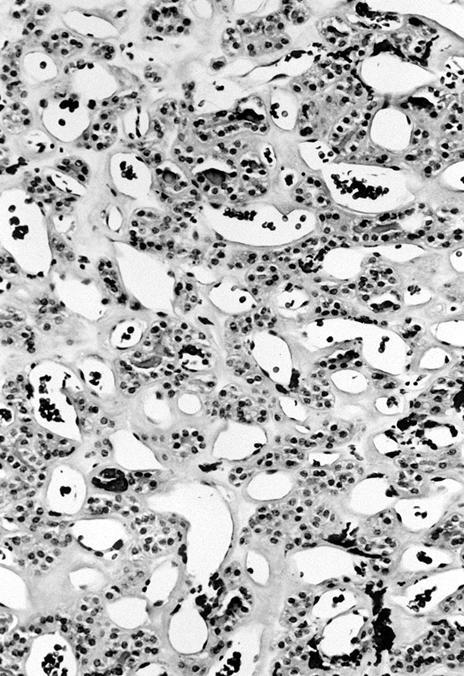

Microscopic (histologic) description

- Architecturally and cytologically different from surrounding gland

- Compression signs in surrounding thyroid tissue

- Encapsulated; thin or moderately thick capsule

- Architectural patterns (can be seen in any combination)

- Normofollicular (simple): size similar to normal thyroid follicles

- Microfollicular (fetal): smaller follicles, small amount of intraluminal colloid

- Macrofollicular (colloid): large follicles, flattened epithelium, abundant colloid

- Solid / trabecular (embryonal): minimal or no colloid

- Focal papillary pattern, occasionally; especially in hyperfunctioning adenoma and follicular adenoma with papillary hyperplasia

- Cuboidal to low columnar cells

- Small round nuclei, smooth nuclear boundary, uniformly hyperchromatic or euchromatic, dense chromatin, absent nuclear features of papillary thyroid carcinoma, nuclear score 0 or 1 (JAMA Oncol 2016;2:1023)

- Inconspicuous nucleoli

- Rarely, lipid filled vacuoles in cytoplasm

- Mitoses are uncommon

- Scant stroma

- Secondary changes: fibrosis, hyalinization, hemorrhage, hemosiderin deposition, edema, cystic degeneration, calcification, osseous or cartilaginous metaplasia

Microscopic (histologic) images

Contributed by Shipra Agarwal, M.D., Andrey Bychkov, M.D., Ph.D., Mark R. Wick, M.D., Asmaa Gaber Abdou, M.D. and AFIP

Patterns: